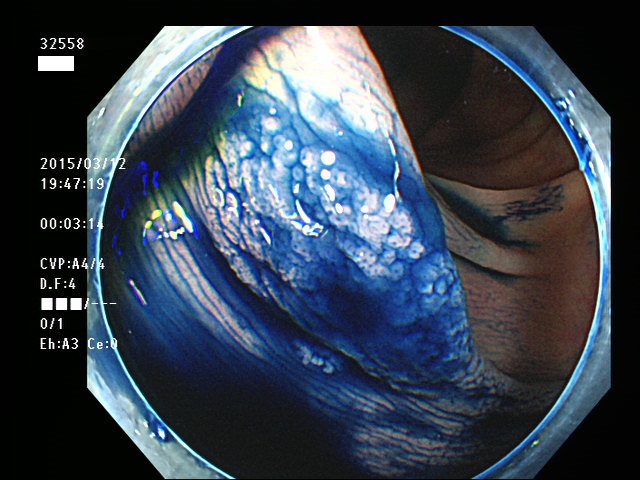

上記100名より抽出した平坦・陥凹型腺腫(=癌化の危険が高いが見落としやすい病変)の内視鏡写真

32550 32553 32555 32556 32558 32559 32560 32562 32563 32564 32568 32569